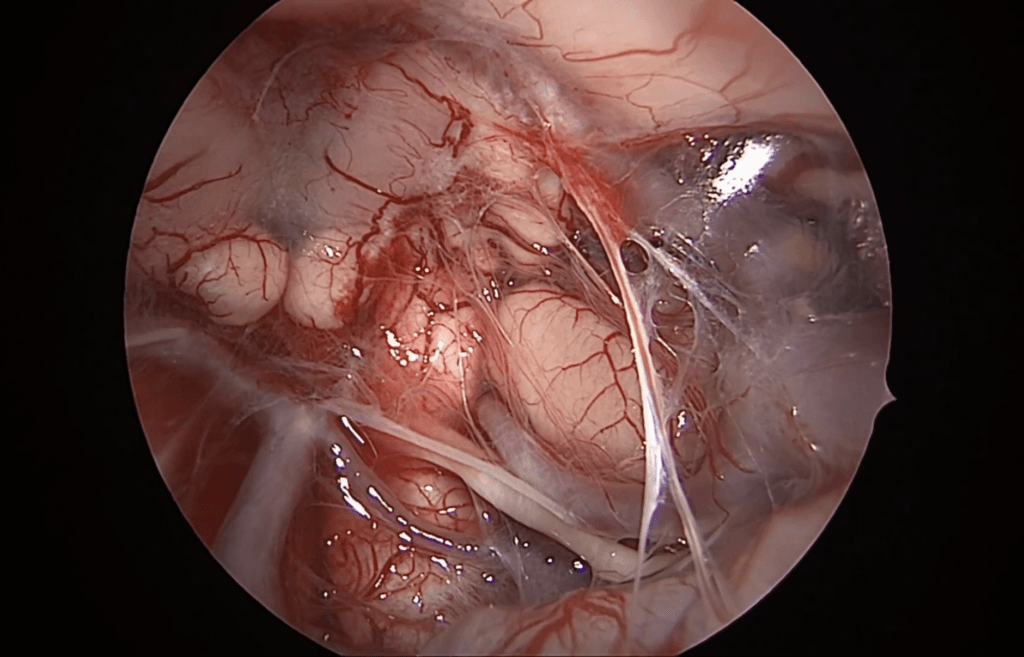

Resección de neurinoma del acústico por abordaje translaberíntico

El Dr. Rubén Polo realiza resección microquirúrgica de neurinoma del acústico por abordaje translaberíntico.